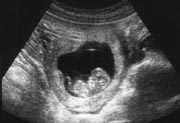

超音波で見た10週の胎児。

これまでは胎芽(たいが)と呼ばれていたけれど、妊娠8週からは胎児になります。

このような超音波検査で、妊娠9、10、11週に赤ちゃんの頭からおしりの長さを測り、妊娠予定日を出します。